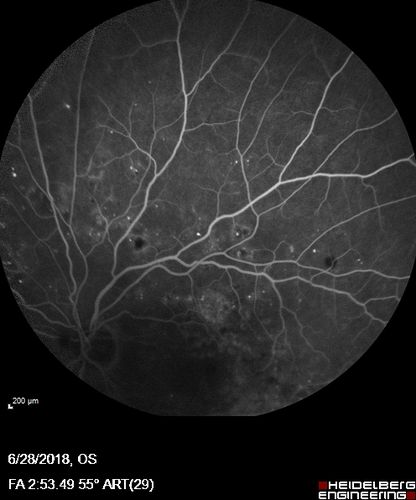

Diabetic Macular Edema with Exudates

Patient did not want injection therapy and did well with laser